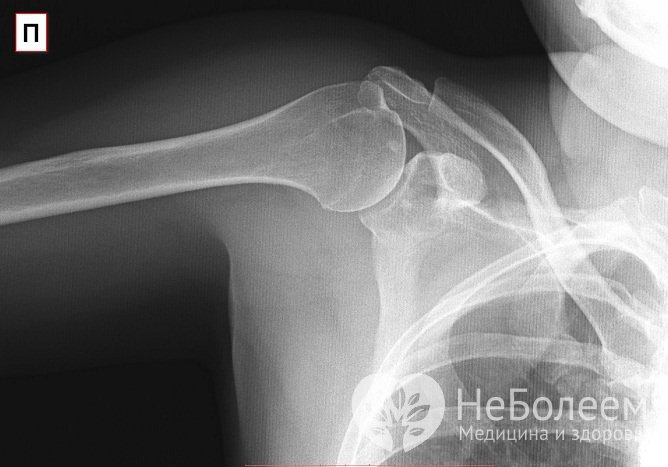

Характерные симптомы артроза плечевого сустава обнаруживаются главным образом в ходе рентгенографии, МРТ и КТ. Для начального этапа заболевания характерна кольцеобразная форма суставной впадины – т. н. симптом кольца. На второй стадии на рентгеновских снимках плеча просматриваются характерные изменения суставных структур: сужение суставной щели, субхондральный отек, склеротические очаги, утолщение суставной капсулы и головок костей, появление остеофитов.

Предположительный диагноз ставится ортопедом или ревматологом на основании данных физикального осмотра с учетом анамнеза и жалоб пациента; также проводятся функциональные пробы с нагрузкой на плечо. В целях визуализации специфических изменений в хрящевой и прилегающей костной ткани назначается рентген плеча в аксиальном и переднезаднем положении. На ранних стадиях заболевания требуется проведение МРТ и КТ из соображений более качественной визуализации незначительных изменений в хрящевой ткани. Для выявления воспалительного процесса необходимо сдать общий и биохимический анализ крови и общий анализ мочи.